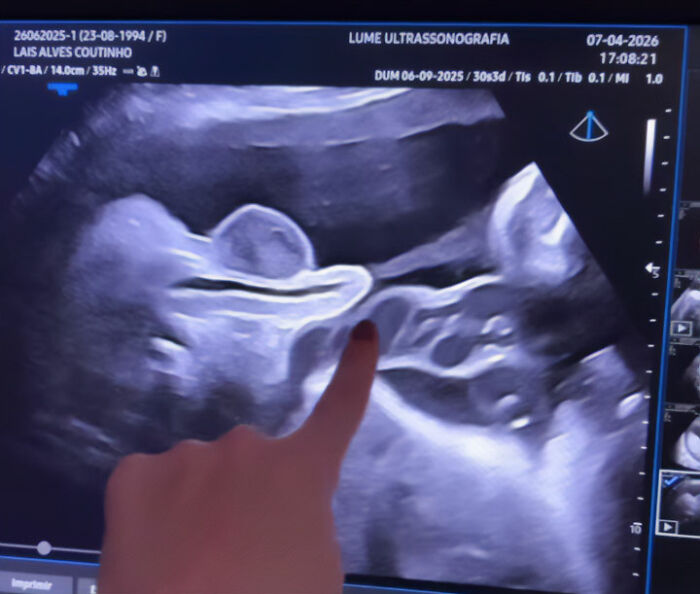

This month, a pregnant doctor named Lais Coutinho sparked curiosity by sharing an ultrasound that captured the exact moment her son peed inside the womb.

- Pregnant doctor Lais Coutinho shared a viral ultrasound video showing her fetus urinating inside the womb.

A doctor went viral after showing an ultrasound of her fetus urinating in the womb

The video has amassed millions of views, igniting interest in how bodily functions work before birth.

Image credits: dralaiscoutinho

“Fetal urine production begins in early pregnancy and becomes more established by the end of the first trimester (around 10–12 weeks),” Khalil explained.